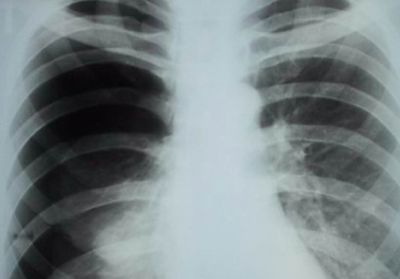

Пневмония

Характер и локализация боли

Правостороннее воспаление легкого характеризуется тупой болью в правом боку, локализованной преимущественно в подреберье.

При длительном течении заболевания боль ощущается в груди и спине со стороны пораженного органа.

Дополнительные симптомы

Первым симптомом пневмонии является резкое повышение температуры до значительных отметок (до 39,5 °С). Далее пациенты отмечают признаки общей интоксикации, которые включают в себя:

Диагностика и лечение

При возникновении описанных выше симптомов необходимо обратиться к пульмонологу, который проведет осмотр и сбор анамнеза и назначит дополнительные диагностические процедуры, включающие:

- рентгенографию;

- КТ;

- фибробронхоскопию;

- клинические, биохимические и бактериологические исследования крови и отделяемой мокроты.

Лечение пневмонии проводится в условиях стационара под наблюдением медперсонала.

Медикаментозная терапия состоит из применения антибиотиков, витаминов и микроэлементов, отхаркивающих препаратов и бронхорасширяющих средств.